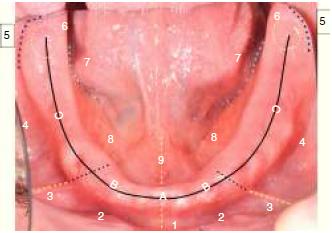

After the definition of the anatomical sites, two diagrams were made, one for the maxilla and one for the mandible (Figs. 1 and 2). The students were asked to register the presence or absence of lesions during each control. In the case of the presence of lesions, students had to color with yellow erythematous lesions and mark with red ulceration areas. Along with this, the perception of pain of the patient at the time of the control was recorded using the numerical verbal scale (EVN), in which patients qualify pain with a number between 0 and 10, 0 being ‘‘no pain’’ and 10 ‘‘worst pain imaginable’’.

Zones of distribution of ulcers in mandible: 1: Medial lower frenulum, 2: Anterior vestibular flank, 3: Side bridle, 4: Posterior vestibular flank, 5: Distovestibular area, 6: Piriformis papilla, 7: Posterior lingual flank, 8: Anterior lingual flank, 9: Lingual frenulum, A: Corresponds to the high area of the flanges, located in relation to the place of insertion of the middle bottom bridle. B: Corresponds to Upper flanges, located between the insertion of the middle bottom bridle and side bridle. C: Corresponds to Upper flanges, located by distal to the insertion of the middle bottom bridle.

In mandibular jaws, a total of 164 adjustments were made, of which 40.9% were carried out during the first control, 32.9% during the second, and 18.9% during. 16.5% of the lesions were observed on the anterior lingual flank, being the site of highest prevalence. On the posterior lingual flank and anterior vestibular flank a 13.4% of lesions was observed. The fourth highest affected site was the distovestibular angle with an average of 12.8% (Fig. 4).

Diagram of topographic location of mandibular trauma injuries, ordered consecutively according to frequency of appearance.